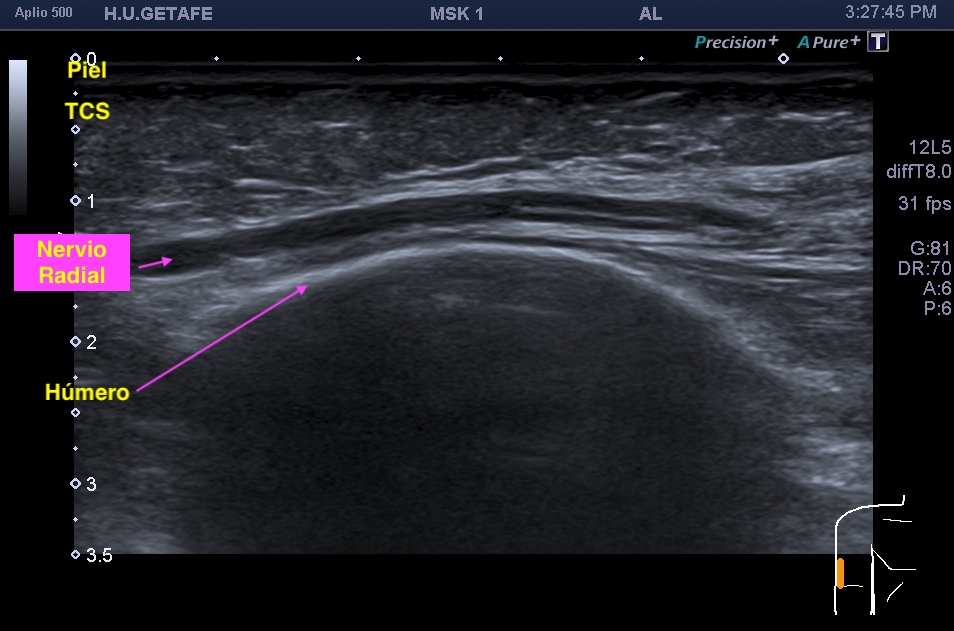

En la mayoría de los casos que el paciente comenta dolor en la parte postero lateral del brazo en el tercio medio la exploración ecográfica es normal, pero ojo si encontramos estas imágenes que vas a ver a continuación, debemos comentarlas y documentarlas ya que hablan por si mismas:

Semiológicamente el patrón normal de un nervio tiene aspecto de un cable que cortamos por la mitad y vemos como sus hilos conductores están seccionados en eje corto y alargados en eje largo. Su aspecto es ligeramente hiperecogénico. Cuando pierde su ecoarquitectura normal se vuelve hipoecogénico y aumenta su grosor, exactamente igual que tienes en la imágenes que has podido estudiar previamente.